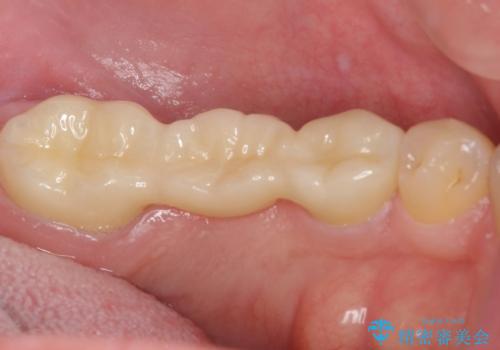

できるだけ外科処置は避けたいという患者様の希望と、すでにブリッジの土台となる両隣の歯を削って治療していることを考慮し、患者様と相談の上、今回はインプラントではなくフルジルコニアブリッジで治療することとしました。

より外れにくく精度の高いブリッジにするため、事前に親知らずの抜歯を当院で行いました。

外れる心配がなくなって安心して食事ができるとおっしゃっていました。